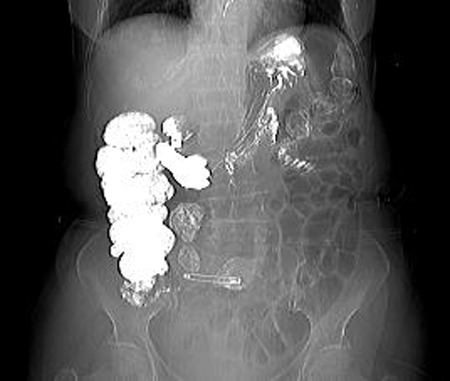

(喝水的重要性病例展示:胃癌患者,胃腔未充盈之前,病灶不能显示;喝水充盈胃腔后癌病灶显示清楚)。

(备注:行钡餐检查过的患者,钡剂残留胃肠道内,伪影干扰较大,腹部脏器结构显示不清,影响检查效果,需另行预约CT检查时间)